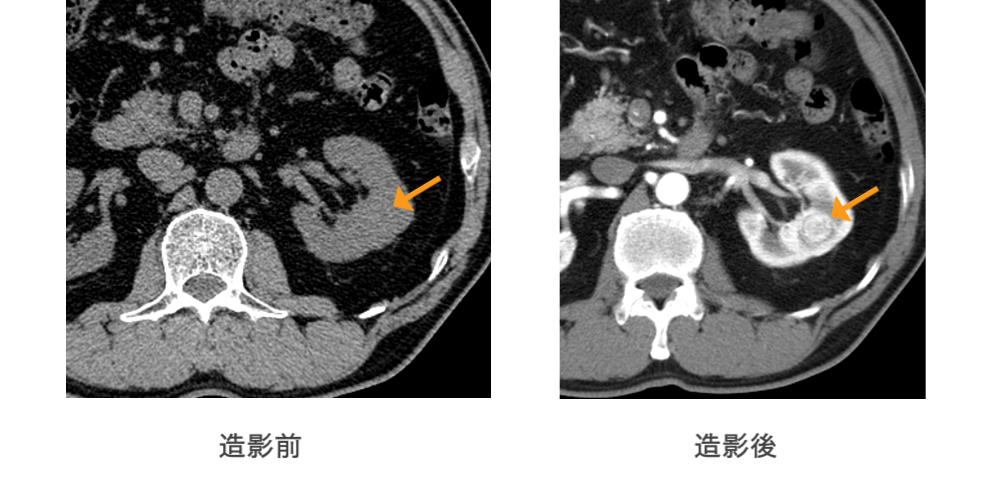

造影剤を血管内に投与することで、コントラストのついた画像を得ることができ、非造影CTでは診断不可能な病変を検出することができます。

非造影では認識できない病変が造影後は明瞭に認識されます。

(腎癌の症例)